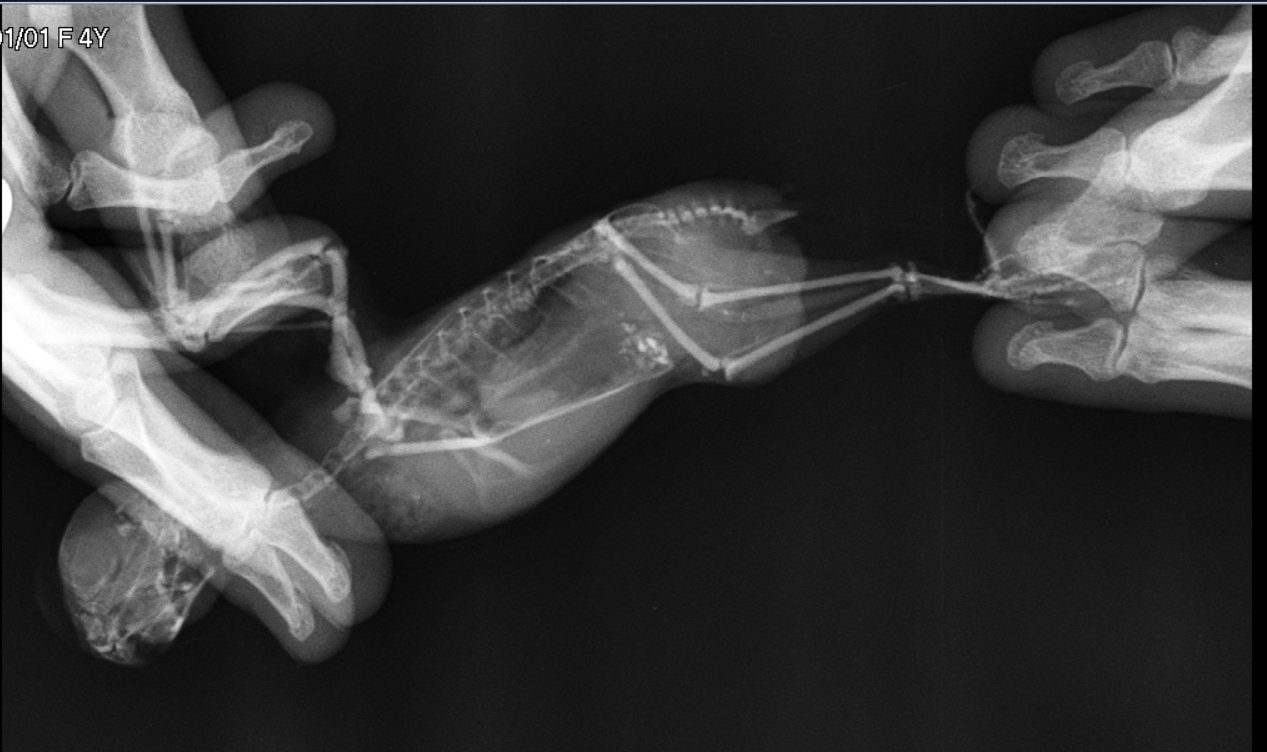

Волнистый попугай Самка, 3 года Зерносмесь Престиж (Бельгия), сенегальское просо РИО, минкамень, сепия, минеральная смесь РИО, фрукты-овощи, каша вареная (гречка+рис не шлифованный+геркулес), Vinka+кальций 2 раза в год при линьке Клетка ферпласт, в большой светлой комнате около стены, на уровне глаз, световой день лето 14 часов, зима 11 часов (режим соблюдается постоянно) 20.05.18 обнаружена шишка внизу и немного слева на животе. Выросла за 1 день буквально. Помет укрупнился и стал реже, птица тужится при этом. Стала быстро утомляться, после полетов появилась отдышка. Хвост немного опущен и двигается в такт дыханию. Аппетит есть. До этого я заметила, что восковица перестала коричневеть уже около года не меняла цвет, но не придала этому значения, птица живет без самца. 24.05.18 попали на прием в Кобру, сделали рентген. Мнение доктора-это липома, но, возможно, есть и злокачественное образование, т.к. на снимке видны затемнения. Прописала 2 капли в день (утро и вечер) суспензию Локсиком для начала, далее идем на повторный прием в субботу 26.05.18. Локсиком принимаем, визуально по птице реакции на препарат не вижу (отдышка после полетов не ушла, когда отдыхает дышит тяжело периодически). Посмотрите, пожалуйста, рентгены со своей стороны, Ваше мнение - видны злокачественные образования или нет? Какую порекомендуете схему лечения?